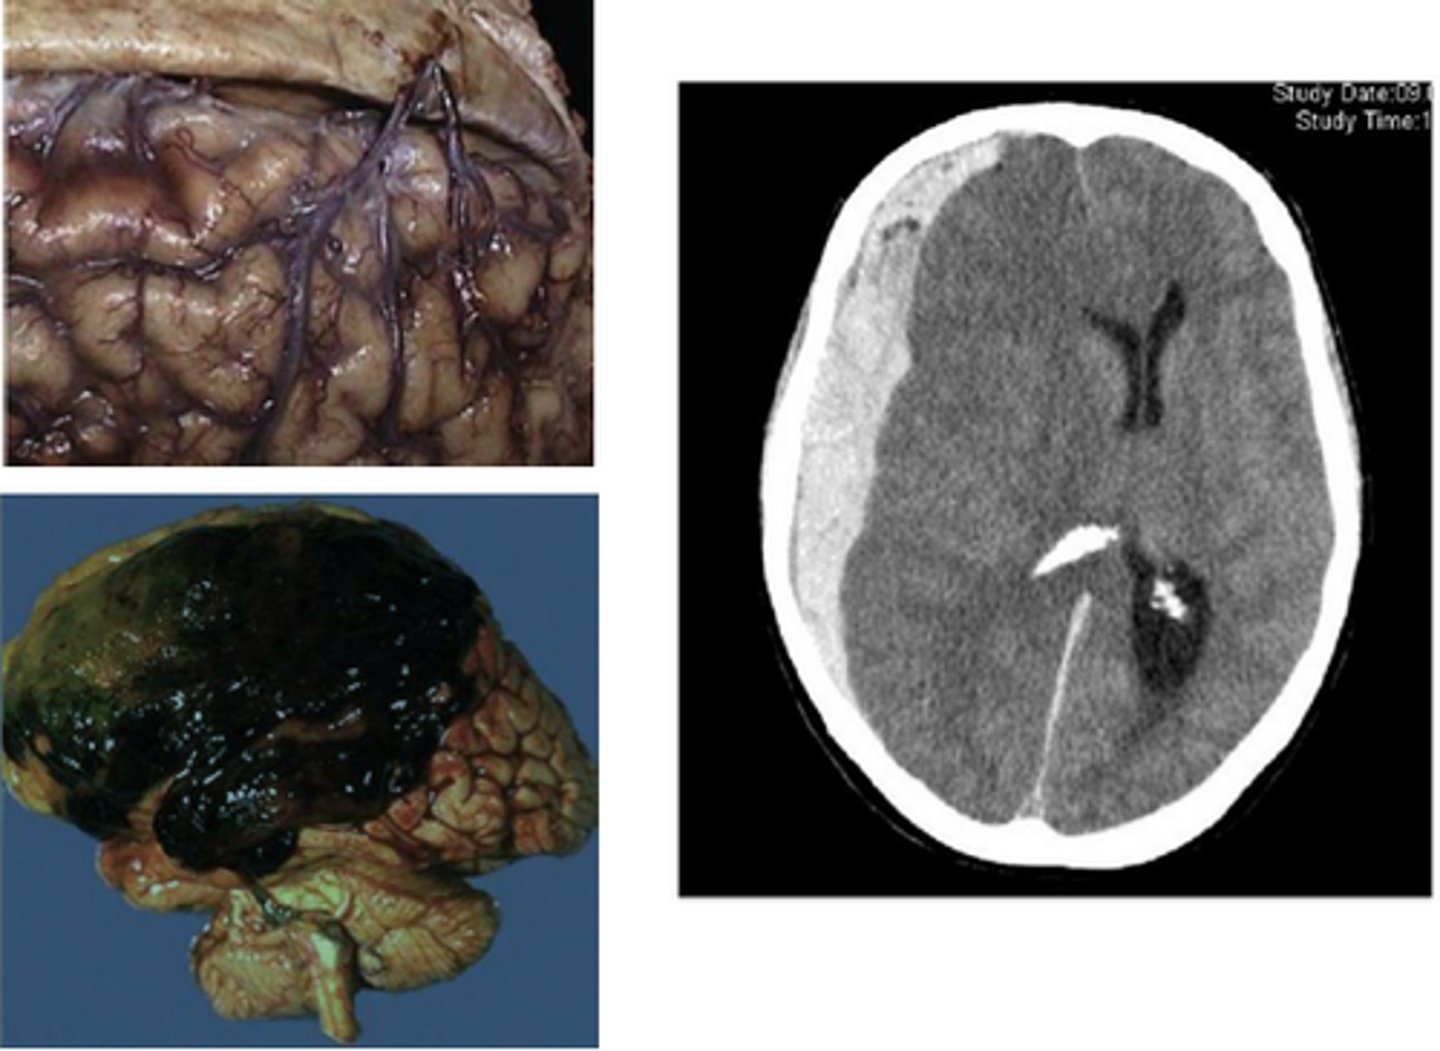

Subdural hematoma are common in ___.

Older patients

Alcoholics due to brain atrophy + vessel fragility

Blunt or shearing trauma tears bridging veins, causing them to bleed into the subdural space

Hemorrhages are seen as [hyper/hypo]dense areas on CT scan, while infarcts are [hyper/hypo]dense parenchymal areas on CT scan.

Hemorrhages = Hyperdense

Infarctions = Hypodense